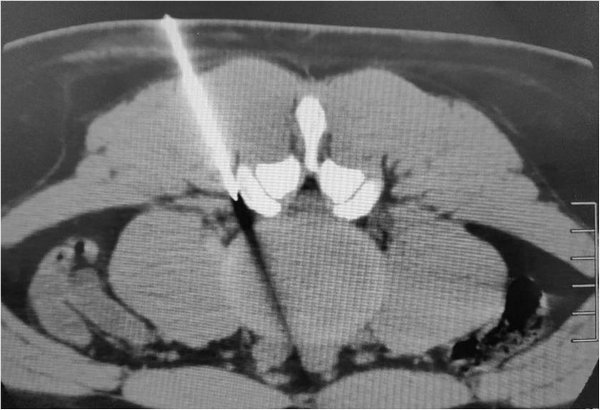

CT引导下选择性腰、骶神经根阻滞术是在CT机引导下,对可能引起神经根痛的病变神经进行穿刺阻滞的微创技术,由于CT扫描软组织分辨率高,可清晰显示神经根、背根神经节和周围组织结构,在CT引导下能准确选择最佳穿刺点、穿刺角度及深度,使针尖准确到达神经根周围位置,并能避开血管等重要结构,使手术安全、准确,用药量少,并大大降低了并发症的发生率。

穿刺针刺入左侧L4神经根周围脂肪间隙内